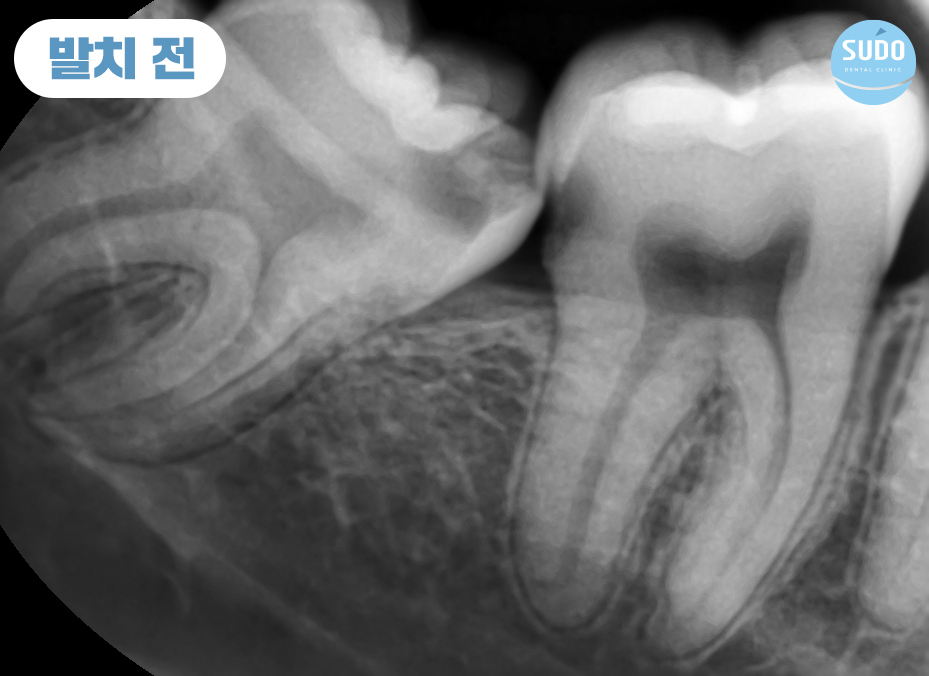

본 환자분은 20대 초반의 남성분으로 오른쪽 아래 매복되어 있는 사랑니에 충치가 심하게 진행되어 치아 일부가 이미 파절된 상태로 본원에 내원해 주셨습니다.

X-ray를 촬영해 보니 치아 뿌리 끝이 신경관과 매우 근접한 상태였습니다. 신경관 손상 가능성이 있어 까다로운 케이스였는데, CT로 촬영하여 정밀 분석한 결과를 토대로 환자분의 충분한 상담을 통해 발치를 진행하기로 했습니다.

다른 영구치와 같이 정상적으로 맹출하면 잇몸의 절개 없이 비교적 간단히 발치가 가능하지만, 비정상적으로 맹출하거나 턱뼈 속에 매복되어 있는 형태의 경우에는 잇몸을 절개하는 과정과 더불어 뼈 삭제를 동반한 발치가 필요하기 때문에 매우 섬세한 치료 중 하나입니다.

특히, 본 환자분과 같이 신경관과 가까이 위치했다면 난도가 높은 과정이 필요한 만큼 의료진의 선택이 더욱 중요해집니다.

파노라마 사진에서 보이는 것과 같이 아래쪽 어금니 아래는 많은 신경들이 지나갑니다.